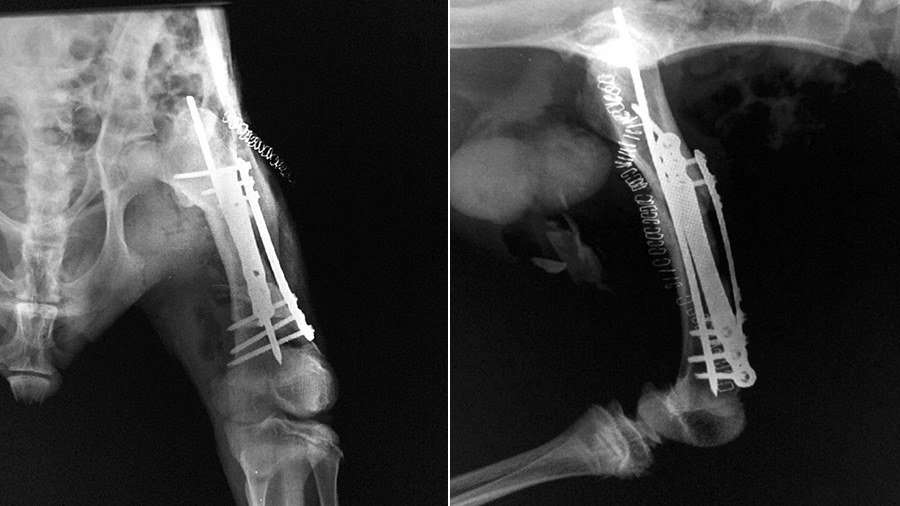

Using an intramedullary pin associated with double locking plates (rod and plate configuration) the fracture was bridged without an attempt to achieve perfect anatomic reduction but just focusing on the correct alignment.

“I had to identify similarities of anatomical structures. Some were different from what I was expecting. For example, the shape of the biceps femoris was deceiving and was converging toward what I expected to be the patella,” he said. “I discovered that the kangaroo doesn’t have a patella! I had to place the implant in a position that would not interfere with other anatomical structures, so I placed it as distally as I could. The realignment had to be perfect and the fixation super strong in order to allow the patient to bear weight on the hind limbs as soon as he was awake.”

“This patient presented the same challenge as horses that have had internal fixation of a limb fracture: They have to stand and walk on the leg the moment they wake up from the anaesthesia. But there was just one difference to make it more challenging: The kangaroo stands only on the hind limbs like a human being,” said Alessandro. “You cannot give a crutch to a kangaroo, so we needed a solution for confining the patient postoperatively. Matteo, who is an expert equine surgeon, suggested a wake-up box with padded mats and hay so that’s what we did. All of a sudden, after the surgery, the kangaroo started moving his head and suddenly he was up on two legs, looking around and scratching his belly.”

Within a few weeks, the patient was at the safari park, once again proving the life-changing value of the AO principles.

“The end results were far, far more exciting than I expected. After the patient recovered, you couldn’t even tell which leg had been injured,” said Alessandro. “This case demonstrates that we can do something for these species by just applying the AO principles and using the best available implants for the particular fracture.”